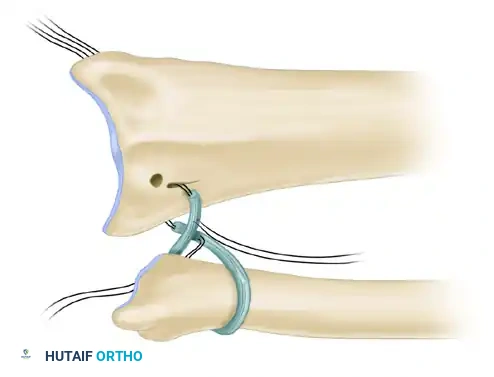

Figure: Dislocation of the radial head demonstrating a ruptured annular ligament. In acute settings, this ligament can often be sutured satisfactorily.

Step 3: Ligament Repair or Reconstruction

* Primary Repair: If the tissue quality is robust, the annular ligament is repaired directly to its ulnar footprint using suture anchors or transosseous sutures.

Figure: If primary repair is impossible, the annular ligament can be reconstructed using a strip of fascia lata passed around the radial neck.

- The graft is passed circumferentially around the radial neck and secured to the anterior and posterior margins of the sigmoid notch through drill holes.

- Tensioning must be precise: tight enough to prevent subluxation, but loose enough to permit full, unhindered pronation and supination.